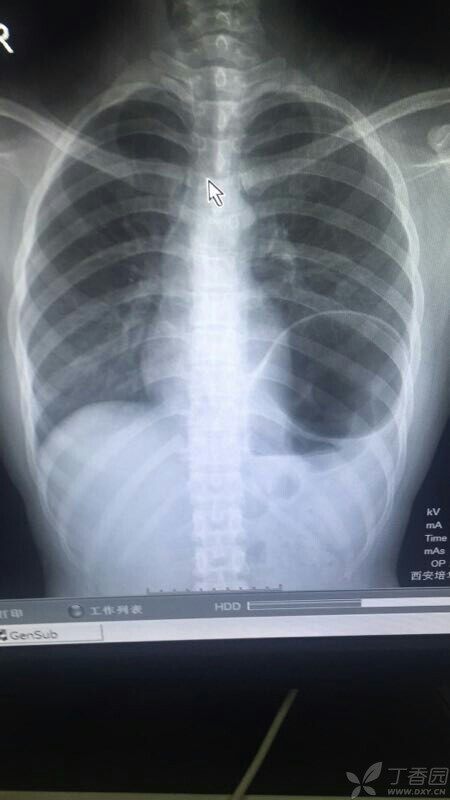

不正常的胸透图片

患者,青年女性,学生,左侧胸痛1周,无任何病史,各位老师,发表一下观点!